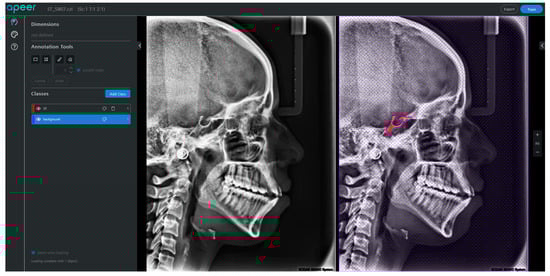

A team consisting of a radiographic specialist and two dental clinicians utilised a cloud-hosted artificial intelligence platform named Apeer to meticulously annotate images pixel-by-pixel, as shown in Figure 3 [24]. This platform allows for the precise storage and annotation of images with high resolution. The process involves saving segmented portions with high accuracy following rough calculations. Then, a precise binary mask is generated by assigning sub-pixel values to the chosen boundary pixels and applying pixel-level morphological operations through border modification. Apeer’s workflow involves re-annotating unmarked pixels, filling the image background with a region-filling technique, clustering pixels with specific labels using a connected component labelling approach, and ultimately saving the mask images for training.

Figure 3. Screenshot of the cloud-based Apeer annotation platform user interface, showing a raw and annotated Cephalometric X-ray image.